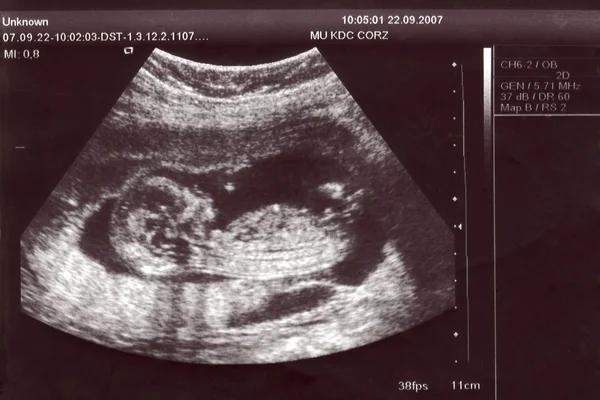

可以。我们机构配有专属孕期管理团队,负责跟进代母从胚胎移植后至分娩的每一个阶段,包括产检、B超、营养、心理状态等。

每次检查后,我们会为客户提供详细的医疗报告、影像资料、翻译总结,确保您远程也能掌握宝宝的发育进展。如有特殊情况或客户需求,也可安排定期视频连线、语音沟通或个别更新频次。

我们以高度负责的态度维护孕期透明度与可控性,让您即使身在异国,也能如同亲临现场般安心和踏实。